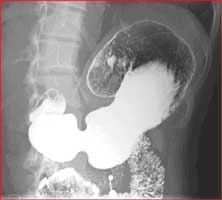

Double contrast barium enema

• Barium Enema: used to examine the large intestine or colon. The test looks at the ascending colon, transverse colon, descending colon and the rectum. The radiologist may able to diagnose ulcers, benign tumors, polyps, cancer or other colonic disorders. The procedure is helpful in assessing for: Chronic diarrhea, blood in stools, constipation, unexplained weight loss and inflammatory bowel diseases, including Crohn’s disease and ulcerative colitis.